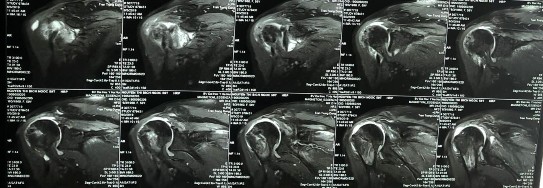

Bệnh nhânn nam 62 tuổi, tiền sử khoẻ mạnh. Bệnh nhân bị chấn thương vai phải sau đập mạnh cầu lông cách nhập viện 06 tháng, sau thấy đau nhiều vai, hạn chế vận động. Do là bác sĩ chuyên về nội xương khớp lên bệnh nhân tự điều trị uống thuốc và tiêm khớp tuy nhiên không thấy tiến triển. Bệnh nhân đến khám và nhập viện ngày 24/02/2020. Khám thấy đau âm ỉ vùng vai, vai hạn chế giạng và đưa trước khoảng 70 độ, hạn chế xoay trong và hạn chế xoay ngoài. Khám các test phát hiện chèn ép khoang dưới MCV và tổn thương gânn chóp xoay thấy: Neer test (+); Speed test (-); Jobe test (+); Patte test (+); Drop arm test (-); Bear Hug test (-), trên phim MRI chụp trước mổ có hình ảnh rách rất rộng và co rút gân chóp xoay đỉnh ổ chảo. Bệnh nhân được tiến hành phẫu thuật khâu gân chóp xoay ngày 25/02/2020. BN sau mổ được mặc áo vai trong 06 tuần, tập phục hồi chức năng. Đánh giá điểm ASES trước mổ và sau mổ là 30 và 96,67 điểm UCLA sau mổ là 33, bệnh nhân rất hài lòng và cảm thấy tốt hơn so với lúc chưa mổ.

Hình phụ lục 2A: Phim CHT bệnh nhân trước mổ cho thấy rách lớn và co rút gân trên và dưới gai trên phim cắt mặt phẳng trán.

(Nguồn: BN nghiên cứu)